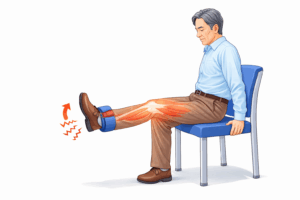

筋力低下

膝を支えている筋肉が弱くなると、膝への負担が増えます。特に重要なのが太ももの筋肉(大腿四頭筋)です。膝の痛みを改善するためには、この大腿四頭筋を鍛えることが重要で、そのため膝の治療ではリハビリがとても大切になります。

リハビリ

膝の治療の土台はリハビリ(運動療法)です。主に、筋力トレーニング・関節の動きの改善・歩き方の指導などを行います。運動療法は変形性膝関節症の診療ガイドラインで強く推奨されており、リハビリによって痛みが改善する方も多くいらっしゃいます。まずここに、しっかり取り組むことが大切です。

Q. 膝が痛いときは運動しても大丈夫ですか?

A. 膝の状態によって異なります。炎症が強いときは無理をしないことが大切ですが、適切な運動は膝の機能改善につながることもあります。特に太ももの筋肉を鍛える運動や関節の動きを良くする運動は、膝の負担を減らす効果があります。状態に合わせたリハビリを行います。